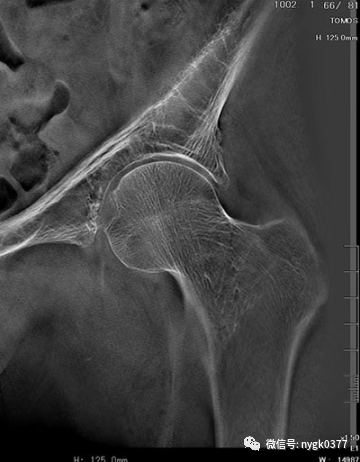

断层融合功能应用在隐蔽性骨折的确诊:

岛津有哪些影像设备岛津 C200拥有性能完善的影像链系统_https://www.jmylbn.com_新闻资讯_第9张

髋关节摔伤骨折确诊